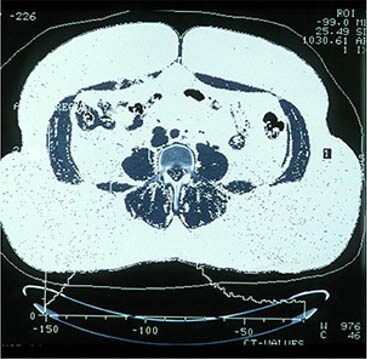

Gojaznost se definirana kao indeks tjelesne mase, tj. BMI („body mass index”), od 30 ili više. Tu vrijednost možete izračunati tako da svoju tjelesnu masu u kilogramima podijelite s kvadratom visine izraženim u metrima.(2) Prije nekoliko godina predstavljena je teorija da se stepen gojaznosti određuje količinom masnog tkiva, a ne tjelesnom masom. Sjetite se samo Arnolda Schwarzeneggera, koji je težio 103 kg godinama, a nije imao ni trunku masti. S druge strane, osoba s istom tjelesnom masom lako može imati veliku količinu nepotrebnih masti. Međutim, važno je gdje se višak masnoće nalazi u tijelu.(3) Dva oblika tjelesne masti su potkožna masnoća i visceralna masnoća. Visceralna se može nalaziti na više područja. Najčešće i najočitije mjesto za pohranu je u području stomaka.(4)

Abdominalna gojaznost ; ustupio dr László Halmy

Potkožna gojaznost ; ustupio dr László Halmy